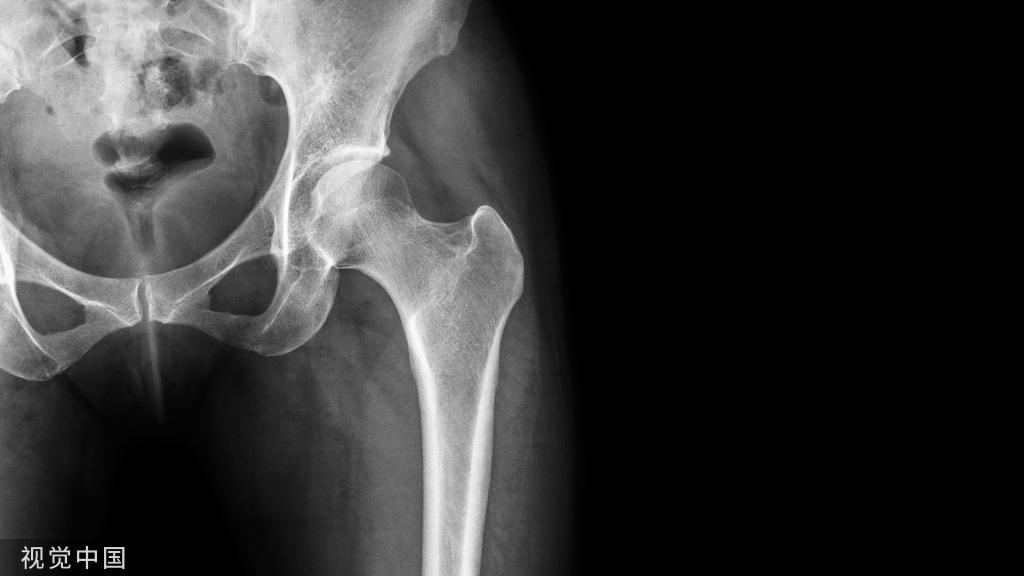

X线片:

X线片在判断脊柱骨结构及序列变化上较其他影像学方法有诸多优势,研究报道椎间盘突出方面的间接征象有局部不稳、椎间隙变窄、代偿性侧凸、牵张性骨赘等(如下)。

但不能直接显示腰椎间盘突出,因此无直接诊断意义,不能作为诊断腰椎间盘突出症的方法(如下)。